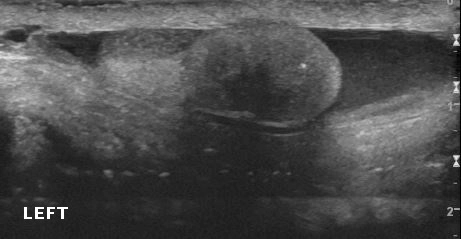

• Bìu và thừng tinh

• Khối u ở bìu